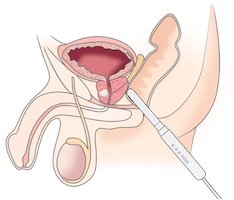

Die TULSA-PRO ist eine MRT-gesteuerte Behandlung der Prostata, die durch die Harnröhre (transurethral) abläuft und einen Prostatakrebs über Ultraschallenergie zerstören kann, die Hitze produzieren. Diese Ultraschallenergie kommt aus einem Behandlungsstab, der ein Ultraschall-gesteuerter Applikator ist und in die Harnröhre eingeführt wird. In dem Behandlungsstab befinden sich 10 Behandlungselemente, aus denen jeweils Ultraschallenergie kommt.

Jedes Element kann einzeln aktiviert werden. Diese individuelle Aktivierung der Elemente ist ideal für eine lokal begrenzte Behandlung eines Prostatakrebses. Zum Beispiel können die Elemente 2, 3, 4, 5 für eine Behandlung in Einsatz gebracht werden, weil der Tumor diese Ausdehnung hat. Die Elemente 1, 6, 7, 8, 9, 10 werden in so einem Fall nicht aktiviert.

Die Behandlung im MRT-Gerät beginnt erst, wenn der Behandlungsstab seine optimale Lage erreicht hat. Das bedeutet, dass die aktivierten Elemente im Behandlungsstab zielgerichtet zum Tumorvolumen liegen. Durch Drehung des Stabes wird der Bereich mit dem Prostatakrebs gezielt behandelt.

Die Ultraschallenergie, die aus den aktivierten Behandlungselementen kommt, verkocht das Gewebe in dem Bereich und trägt es ab (abladieren). Während der Stab aktiv behandelt, schont das System im Stab gleichzeitig die Harnröhrenwand durch ein integriertes Kühlsystem, um keine Schäden durch die Hitze zu verursachen. Zur Sicherheit ist der Dickdarm auch mit einem zusätzlichen Kühlsystem ausgestattet.

Die Behandlung kann während der gesamten Zeit live am Monitor beobachtet und kontrolliert werden.

TULSA-PRO steht für Transurethrale ULtraSchallAblation der Prostata. Transurethral bedeutet „durch die Harnröhre“. Ablation steht für „Abtragen von Körpergewebe“, hier durch Erhitzung. Fokale Behandlung bedeutet, dass nur ein ausgewählter Bereich behandelt wird, um das Organ zu erhalten. MRT steht für Magnet-Resonanz-Tomographie und ist ein Gerät, das Schnittbildtechnik auf Basis von Magnetfeldern und nicht von Röntgenstrahlen durchführt.

Bei dieser Behandlung wird krankhaftes Gewebe in der Prostata verkocht und abgetragen. Das Verkochen erfolgt über Ultraschallwellen, die Hitze erzeugen (bis zu 86 Grad). Der zu behandelnde Bereich wird vorher exakt eingegrenzt, sodass vermieden werden soll, dass gesundes Gewebe, die Nerven für die Potenz und der Schließmuskel für die Kontinenz mitbehandelt werden. Die Behandlung erfolgt innerhalb der Prostata, also durch die Harnröhre und nicht durch ein anderes Organ, wie z.B. Dickdarm. Bei Therapien durch den Dickdarm, ist der Nachteil, dass zwischen der Dickdarmwand und der Prostata die Nerven für die Potenz liegen und zwangsläufig immer mitbehandelt werden. Nerven, die einmal beschädigt sind, können sich nicht wieder regenerieren.

Die organerhaltende Behandlung mit TULSA-PRO führen wir immer fokal durch. Das bedeutet, dass der Bereich mit dem Prostatakrebs gezielt behandelt wird, während der gesunde Teil der Prostata erhalten bleiben kann. Je nach Ausmaß wird ein Viertel (Quadranten-Ablation) oder die Hälfte (Hemi-Ablation) der Prostata behandelt.